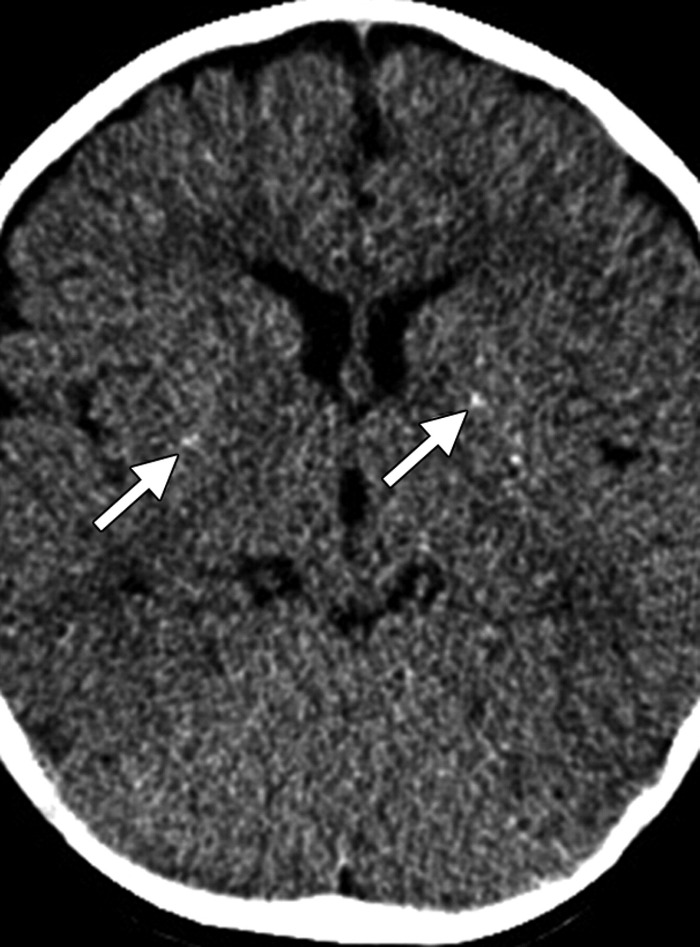

(а) Бесконтрастная КТ, аксиальный срез: у пациента 45 лет с лихорадкой и изменениями психического состояния в медиальном отделе правой височной доли определяется подозрительный участок слабого изменения плотности мозговой ткани.

(б) МРТ, Т2-ВИ, аксиальный срез: у того же пациента в медиальном отделе правой височной доли определяются изменения интенсивности сигнала. При исследовании СМЖ методом полимеразной цепной реакции (ПЦР) был выявлен ВПГ1. На ранних этапах течения герпетического энцефалита может сохраняться нормальная КТ-картина.